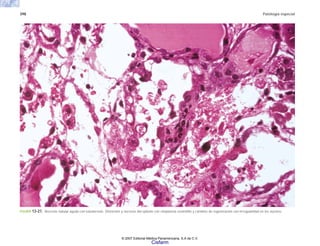

FIGURA 6-31. a) Vasculitis coronaria en un caso de SIDA que muestra necrosis